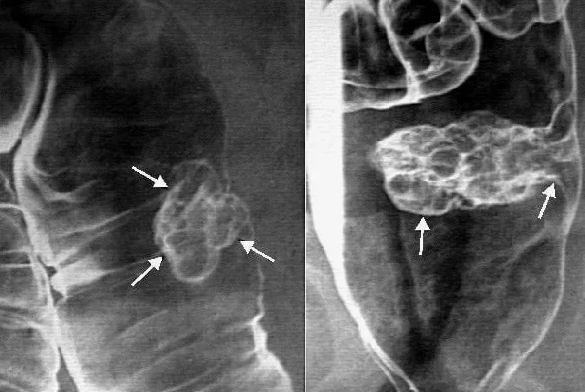

¿Y por qué empeora la circulación sanguínea? ¡El culpable de esto es el colesterol! Sí, ese mismo del que tanto se habla. Por su estructura, el colesterol se asemeja a la grasa fría. Es decir, es una sustancia muy pegajosa. Con los años el colesterol se acumula en los vasos en forma de depósitos en las paredes internas. Además del propio colesterol, en estos depósitos se involucran otras sustancias, que simplemente se adhieren al colesterol.

Todo esto lleva a que, con los años, la capa de colesterol en las paredes de los vasos solo crece. Y debido a ella se reduce la luz efectiva en los vasos. Es decir, aquel espacio por el que fluye la sangre.

Con los años, en todas las personas se acumula colesterol en los vasos, precisamente él reduce el flujo sanguíneo y lleva a que los órganos internos pasen hambre.

Hace literalmente unos años, científicos estadounidenses determinaron el volumen de colesterol en los vasos, que se acumula hacia la edad de 50-55 años. Como se determinó, en promedio en una persona en los vasos se acumula hasta 4 kg de esta sustancia, ¡y la capa en las paredes internas de los vasos puede alcanzar hasta 1 mm de grosor! Esto lleva a que los vasos pequeños se obstruyen completamente, y se excluyen prácticamente del sistema circulatorio, y el flujo sanguíneo a través de los vasos grandes se reduce en un 60-70%.